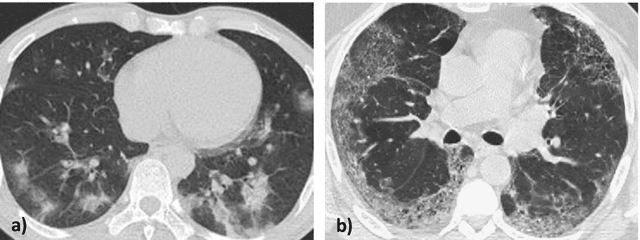

Abstract:OVID-19 is a world-wide disease that has been declared as a pandemic by the World Health Organization. Computer Tomography (CT) imaging of the chest seems to be a valid diagnosis tool to detect COVID-19 promptly and to control the spread of the disease. Deep Learning has been extensively used in medical imaging and convolutional neural networks (CNNs) have been also used for classification of CT images. We propose a light CNN design based on the model of the SqueezeNet, for the efficient discrimination of COVID-19 CT images with other CT images (community-acquired pneumonia and/or healthy images). On the tested datasets, the proposed modified SqueezeNet CNN achieved 83.00\% of accuracy, 85.00\% of sensitivity, 81.00\% of specificity, 81.73\% of precision and 0.8333 of F1Score in a very efficient way (7.81 seconds medium-end laptot without GPU acceleration). Besides performance, the average classification time is very competitive with respect to more complex CNN designs, thus allowing its usability also on medium power computers. In the next future we aim at improving the performances of the method along two directions: 1) by increasing the training dataset (as soon as other CT images will be available); 2) by introducing an efficient pre-processing strategy.